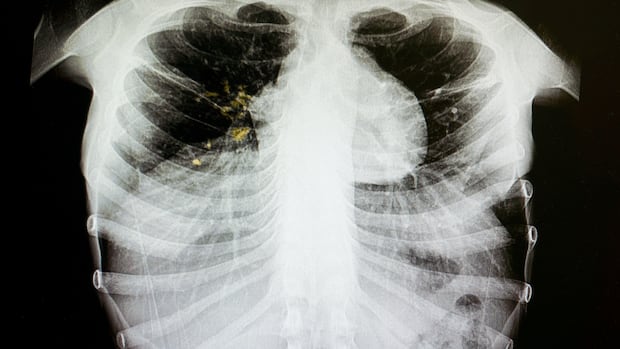

Tuberculosis is an infectious disease that usually affects the lungs, but can affect other parts of the body. It can spread when an infected person coughs, sneezes and spits, but is treatable with antibiotics.